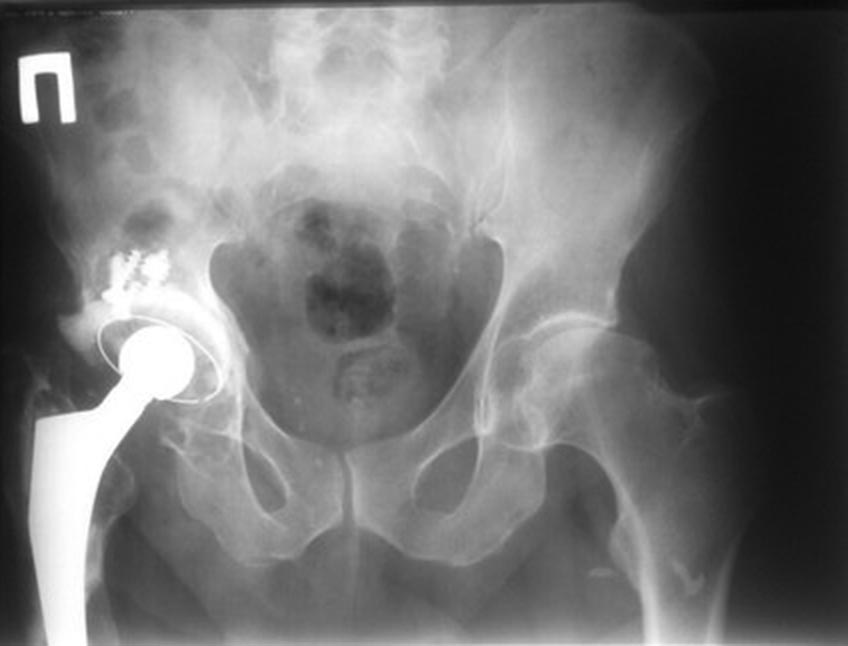

Глубокоуважаемые коллеги! Столкнулся с такой ситуацией. 12 лет назад

пациенту выполнено эндопротезирование ТБС. Паспорта эндопротеза нет. В

течение последнего года беспокоят боли в бедре. Какие варианты

оперативного лечения? Про винты на снимке информации нет, видимо,

пластика крыши. В общем, непростая ситуация.